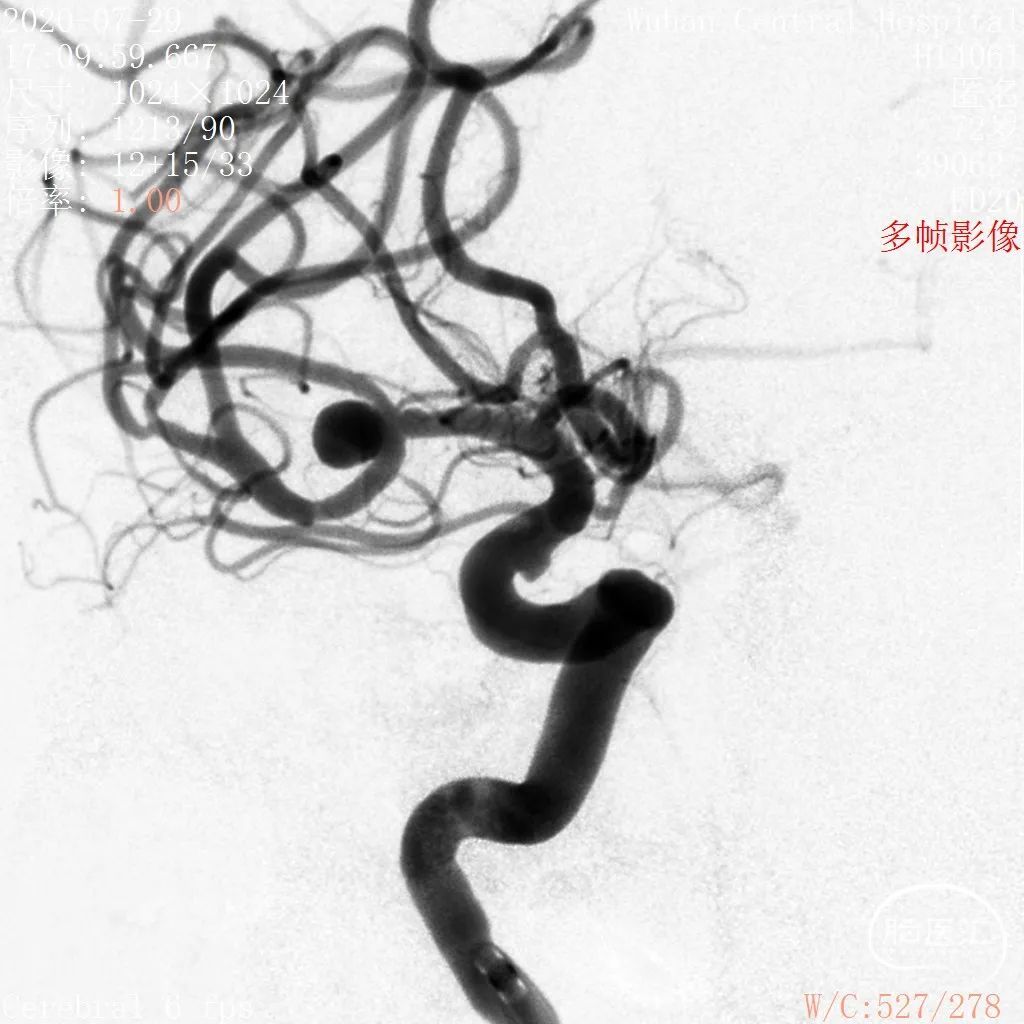

DSA结果:右侧大脑中动脉分叉部动脉瘤,约5.3*5.2mm,颈宽约2.9mm,形态囊状。

术前影像

DSA 2020-07-29